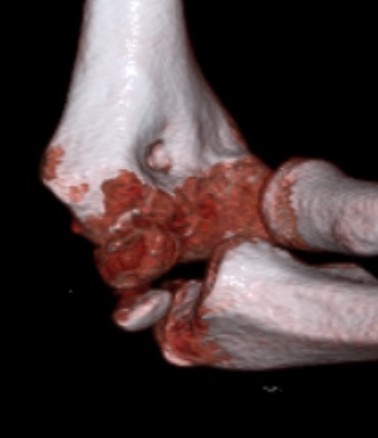

Incarcerated medial epicondyle

- typically elbow dislocation with spontaneous reduction

Incarcerated medial epicondyle fracture

Incarcerated medial epicondyle fragment

Etiology

Elbow dislocation which has self reduced / been reduced

Clinical / Xray

If patient < 5 years may not be ossified

- significant pain

- ulna nerve symptoms

- limited ROM

- absent medial epicondyle on xray / compare to contralateral side

- non congruent joint reduction

- consider CT / MRI / arthrogram / open exploration